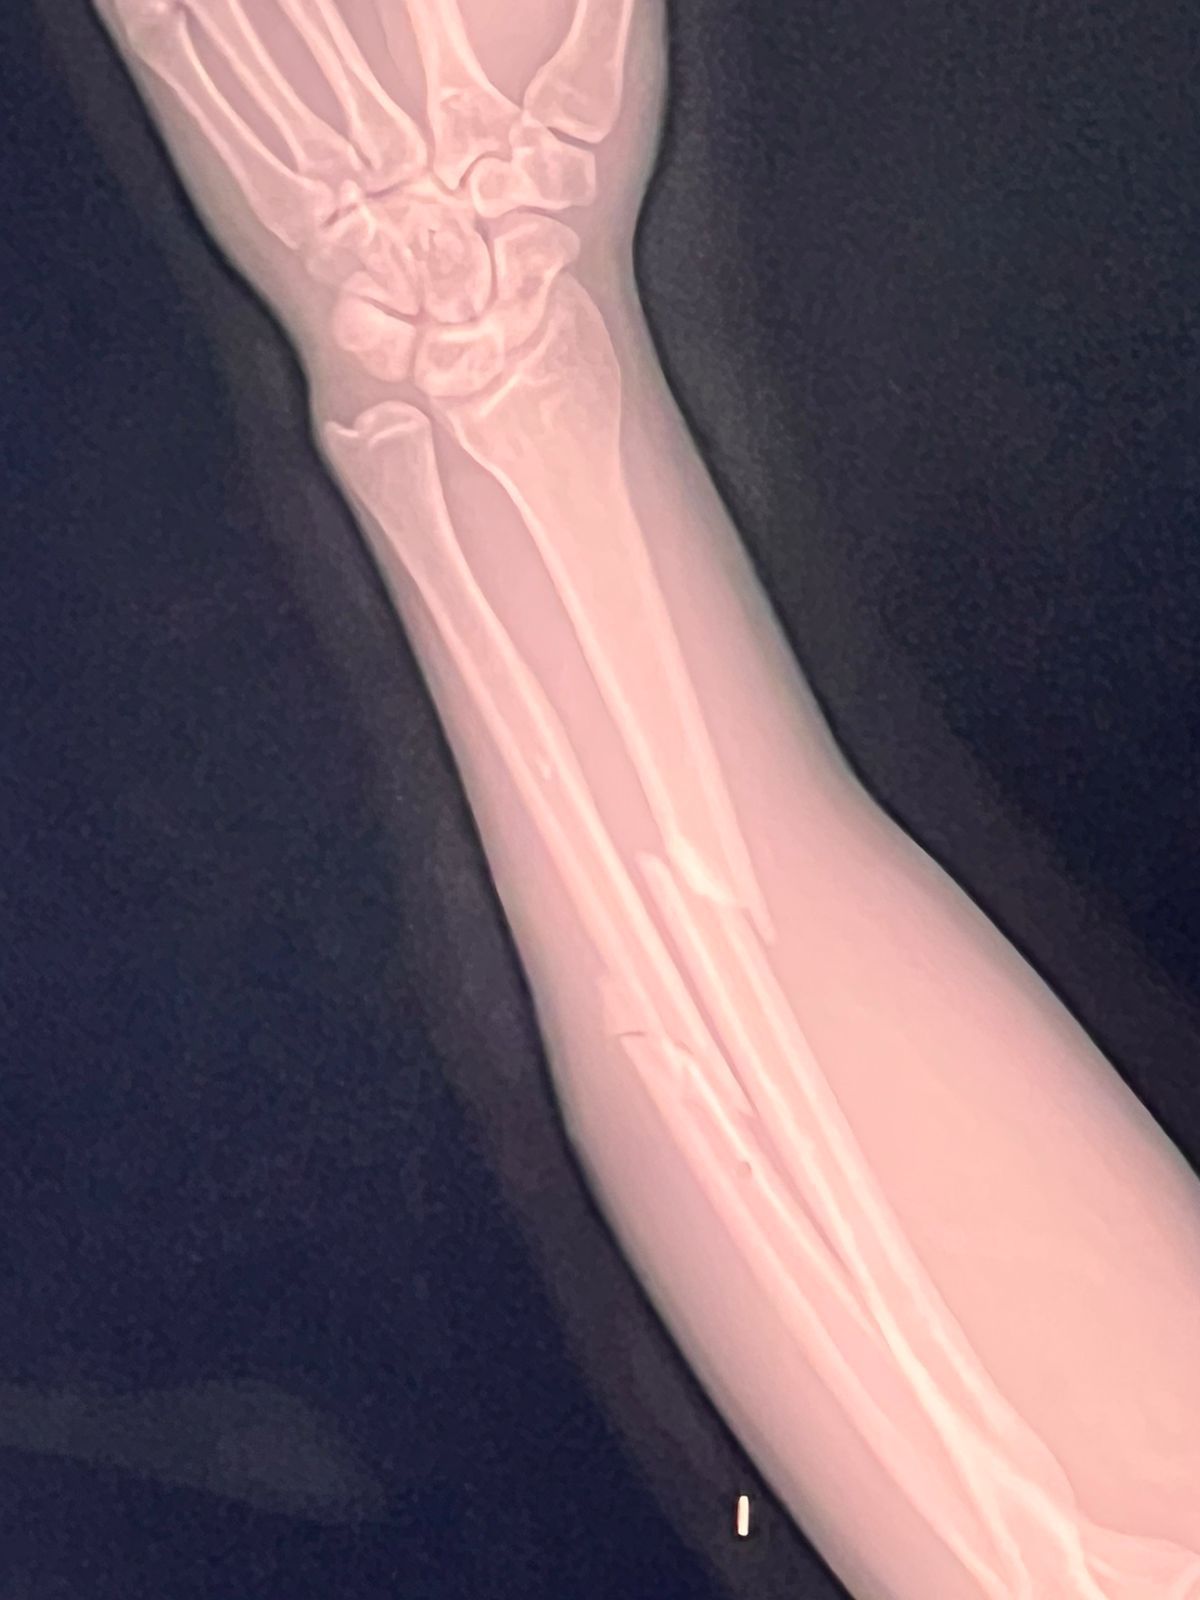

En su intento de evitar la detención el hombre empujó al oficial haciéndolo caer sobre su brazo izquierdo lo que causó fractura de radio y cúbito; el hombre fue intervenido y detenido por otro uniformado de la Policía Municipal presente en el lugar.

Por esta razón fue puesto a disposición de la autoridad que lo requería, mientras que el agente lesionado fue trasladado a un nosocomio para su atención médica correspondiente.